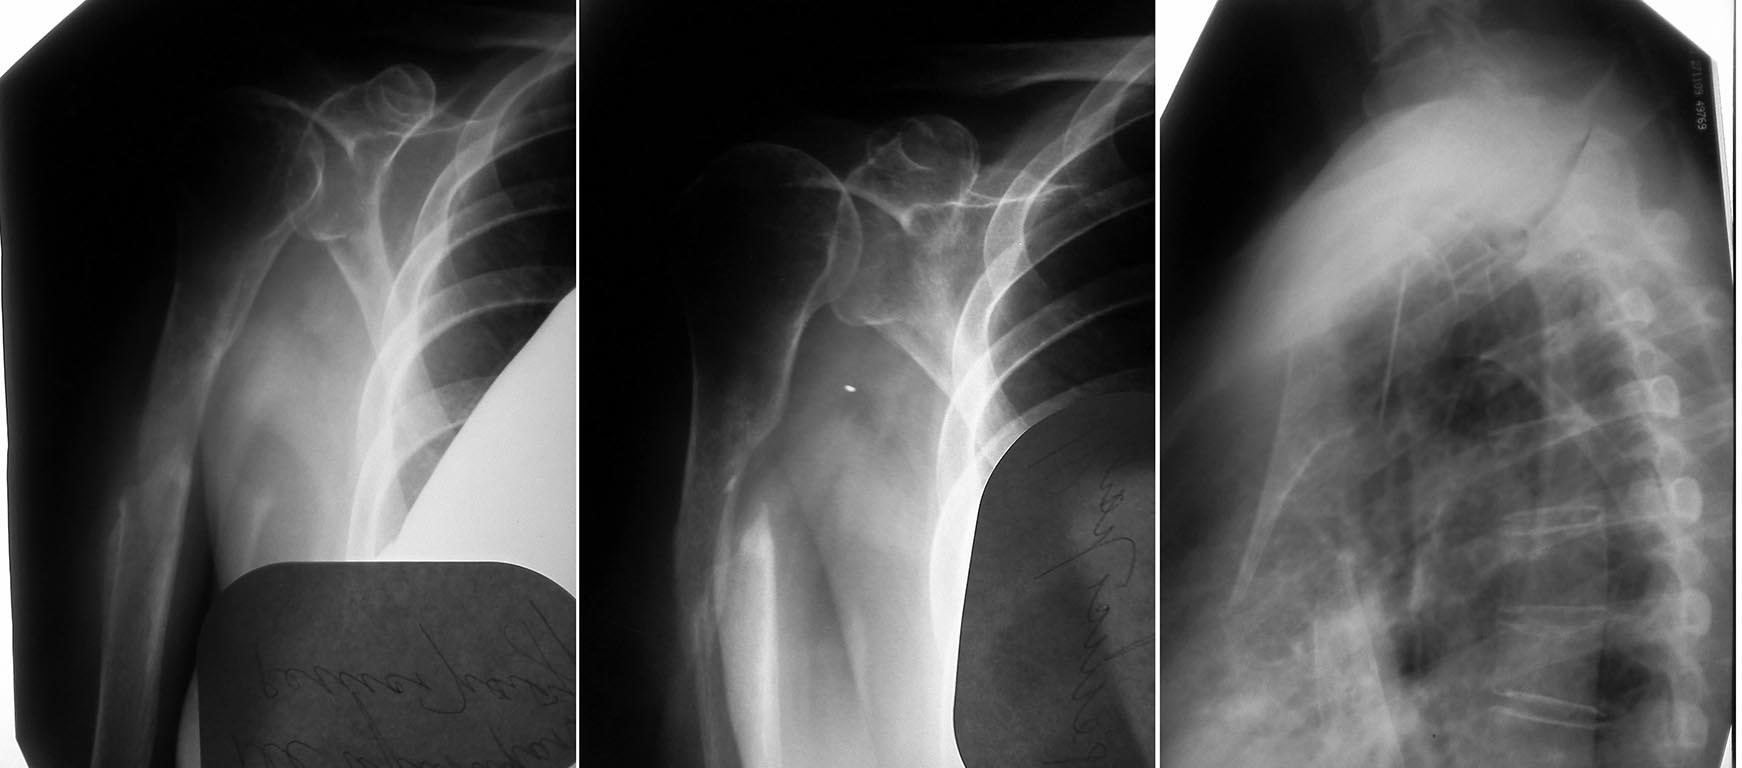

Всем доброго времени суток! В отделение поступила пациентка О. 54 лет. В анамнезе в июле 2011 года перелом верхней трети диафиза правой плечевой кости.

Лечилась консервативно. Гипсовая иммобилизация 6 недель. Результат не был достигнут. К врачам не ходила. На данный момент имеется следующая рентгенологическая картина. Да...... Какие есть варианты по лечению? Остеосинтез пластиной....Укорочение... или в данном случае можно рассмотреть вариант с костной пластикой. Прошу высказать Ваши мысли по данному случаю. Спасибо всем откликнувшимся.